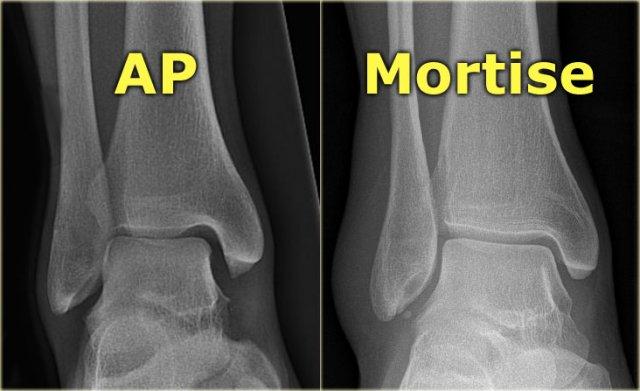

Radiography

Mortise view

Khảo sát X-quang cơ bản của cổ chân bị chấn thương bao gồm tư thế thẳng (AP), tư thế Mortise và tư thế nghiêng.

Tư thế Mortise là tư thế AP được chụp với bàn chân xoay trong 15-25°.

Kỹ thuật viên xoay bàn chân vào trong cho đến khi mắt cá ngoài ngang bằng với mắt cá trong.

Tư thế này giúp quan sát rõ cả khe khớp bên ngoài lẫn khe khớp bên trong.

Trên tư thế AP thực sự, xương sên chồng lên một phần mắt cá ngoài, che khuất mặt bên ngoài của khớp cổ chân.